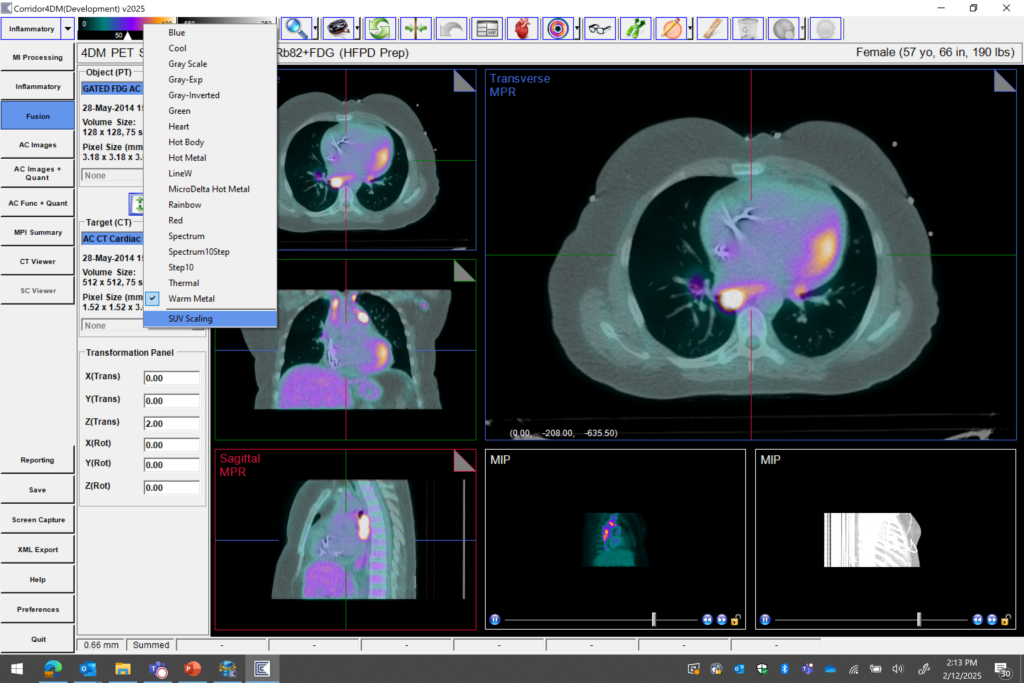

- Inflammation Workflow

SUV tools for cardio-oncology protocols

- Adjust 4DM Color Bar Control from 0 – 100% Standard Uptake Value Range

- Enhances Ability to Identify Abnormalities